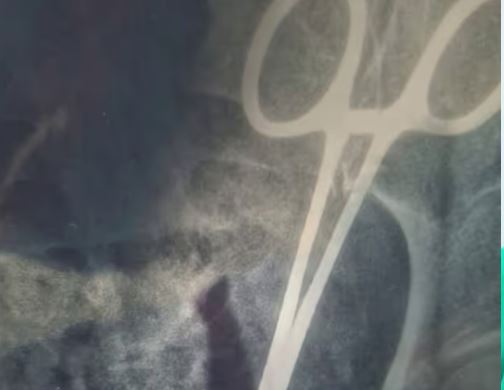

കൊച്ചി: വണ്ടാനം മെഡിക്കൽ കോളേജിലെ ചികിത്സാപ്പിഴവിനെത്തുടർന്ന് വയറ്റിൽ കത്രിക കുടുങ്ങിയ ഉഷാ ജോസഫിന്റെ ശസ്ത്രക്രിയ നാളെ നടക്കും. നിലവിൽ കൊച്ചി അമൃത ആശുപത്രിയിൽ ചികിത്സയിലുള്ള ഉഷയുടെ മകൻ ഷിബിനെ ആരോഗ്യമന്ത്രി വീണ ജോർജ് ഫോണിൽ വിളിച്ച് സർക്കാരിന്റെ പൂർണ്ണ പിന്തുണ അറിയിച്ചു.(Scissors found in woman’s stomach, Usha’s surgery will be performed tomorrow)

ഉഷയുടെ ചികിത്സാ ചെലവ് പൂർണ്ണമായും സർക്കാർ വഹിക്കുമെന്ന് ആരോഗ്യമന്ത്രി ഉറപ്പുനൽകി. കുറ്റക്കാർക്കെതിരെ വിട്ടുവീഴ്ചയില്ലാത്ത നടപടിയുണ്ടാകുമെന്നും മന്ത്രി കുടുംബത്തെ അറിയിച്ചു. ഉഷയുടെ സിടി സ്കാൻ പരിശോധനകൾ പൂർത്തിയായിട്ടുണ്ട്. റിപ്പോർട്ടുകൾ വിശദമായി പരിശോധിക്കാൻ അമൃത ആശുപത്രിയിലെ വിവിധ വിഭാഗങ്ങളിലെ വിദഗ്ധ ഡോക്ടർമാർ ഇന്ന് മെഡിക്കൽ ബോർഡ് യോഗം ചേരും.

മെഡിക്കൽ ബോർഡിന്റെ വിലയിരുത്തലിന് ശേഷം നാളെയാകും വയറ്റിൽ കുടുങ്ങിയ കത്രിക പുറത്തെടുക്കാനുള്ള സങ്കീർണ്ണമായ ശസ്ത്രക്രിയ നടക്കുക. അഞ്ച് വർഷമായി വയറ്റിൽ കത്രികയുമായി വേദന തിന്നു കഴിഞ്ഞ ഉഷാ ജോസഫിന് നീതി ഉറപ്പാക്കണമെന്നാവശ്യപ്പെട്ട് വ്യാപക പ്രതിഷേധമാണ് ഉയരുന്നത്. സംഭവത്തിൽ വീഴ്ച വരുത്തിയ ഡോക്ടർമാർക്കെതിരെ അന്വേഷണം ഊർജ്ജിതമാക്കിയിരിക്കുകയാണ്.